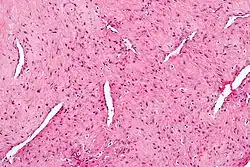

| Micrograph of a nasopharyngeal angiofibroma. H&E stain. | |

Grossly, it is a firm mass that may be yellow, dark red, or even black. Histologically, it presents with several vascular spaces of varying sizes and wall thicknesses as well as fibrous or collagenous stroma with fibroblasts. Mast cells are common. Mitotic figures are usually not present.[5]